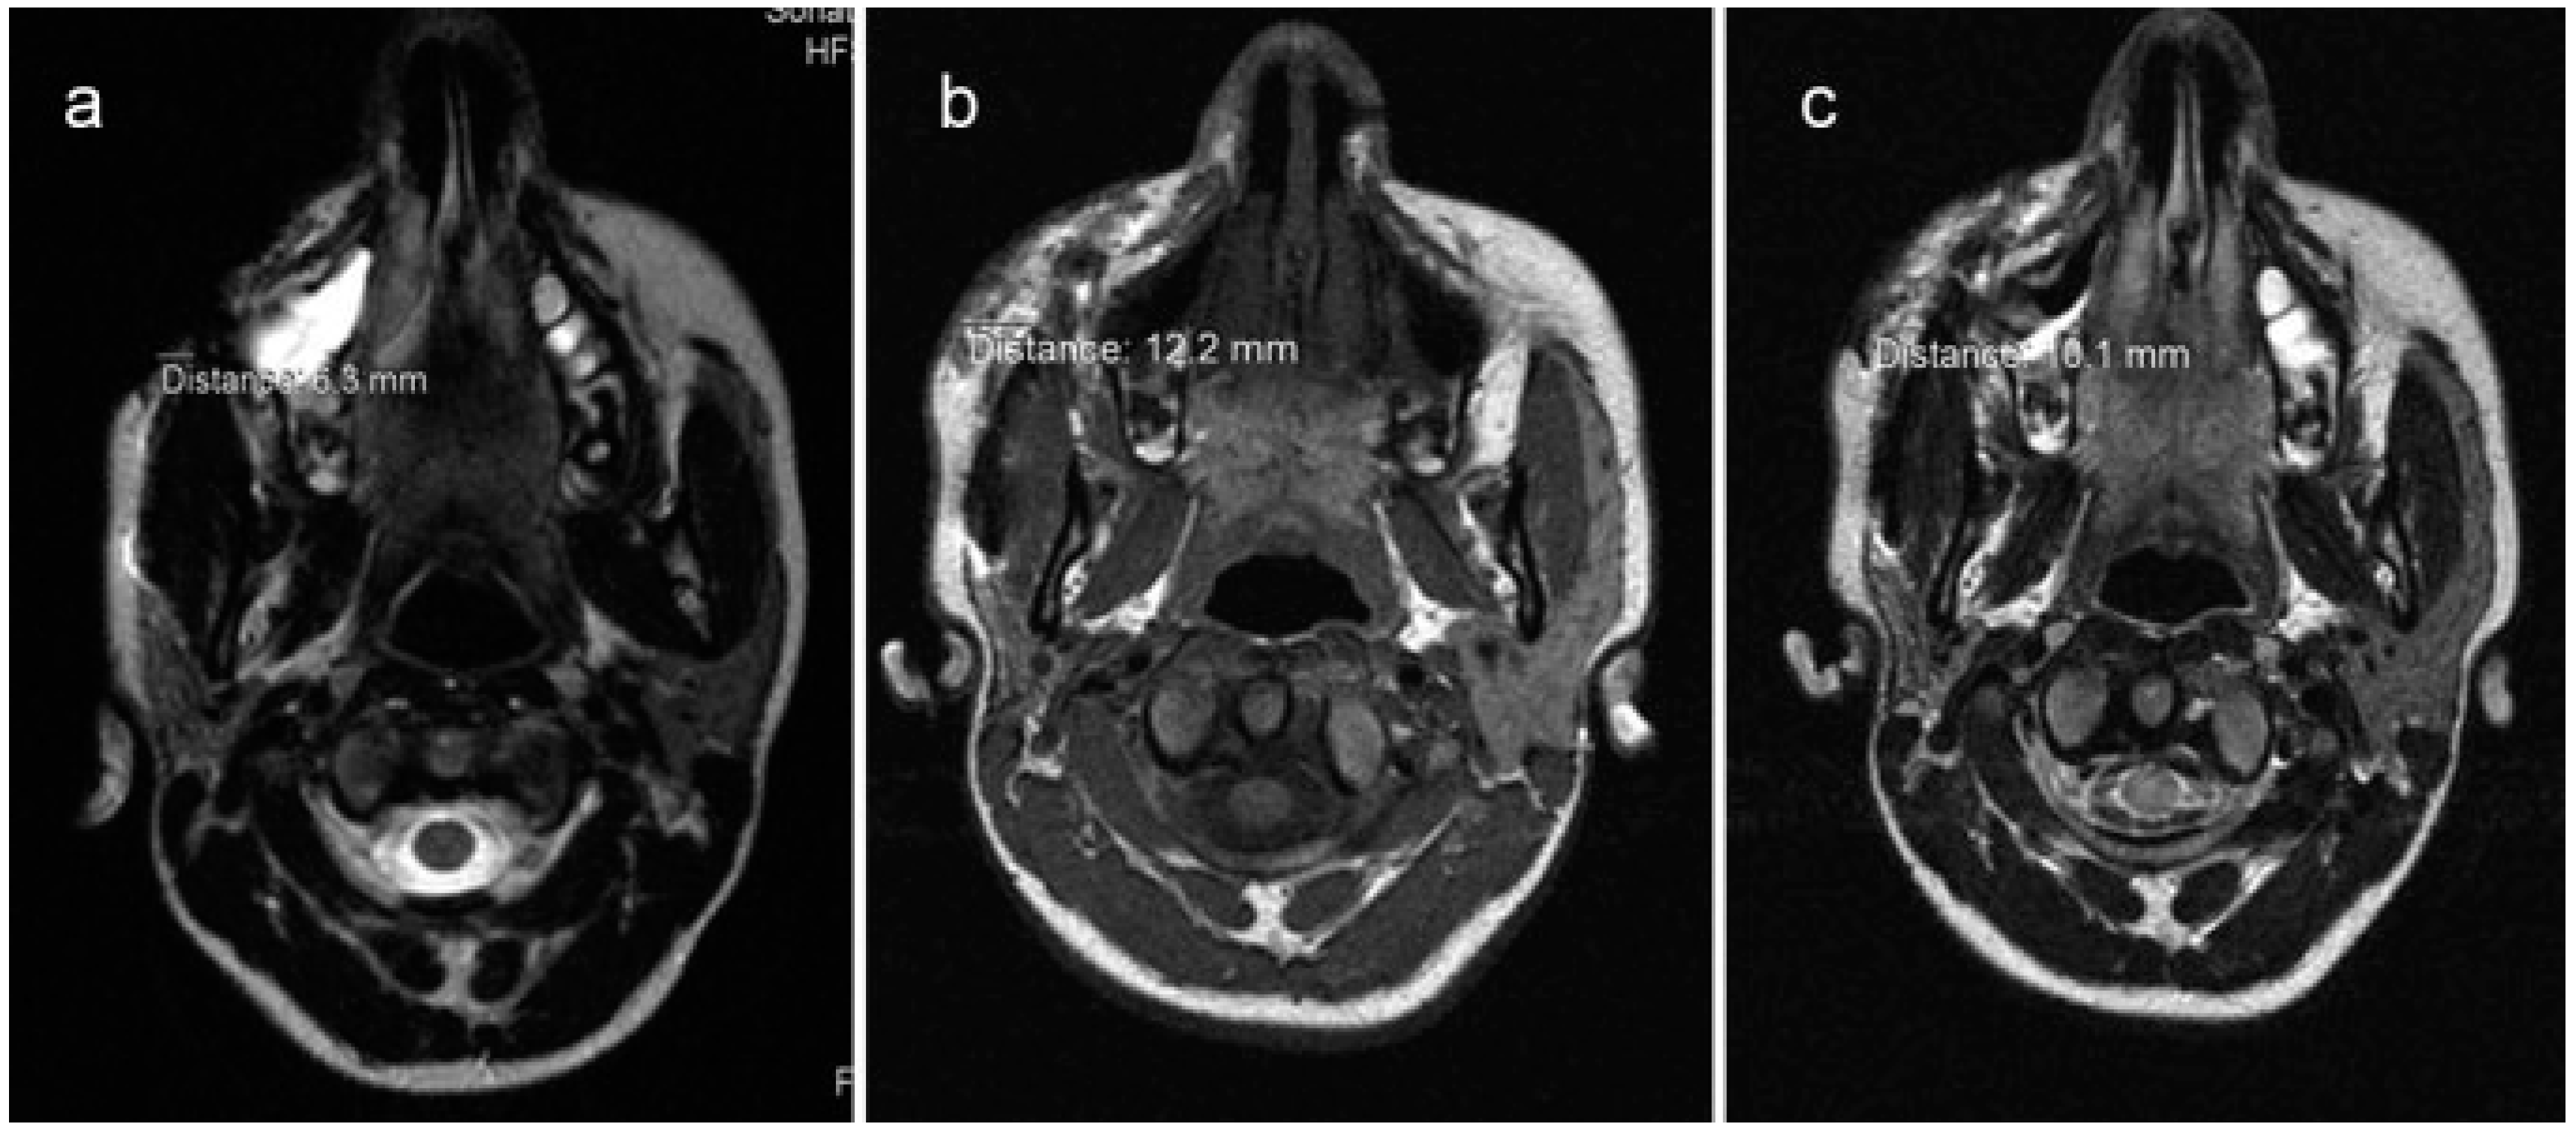

Radiographic evaluations consist of use of MRI done using a 1.5-Tesla Siemens Sonata system (Siemens Medical Solutions, Erlangen, Germany). All patients underwent MRI scans preoperatively and 1st and 12th months postoperatively. Scans were analyzed using RadiAnt DICOM Viewer 1.0.4.4439 (Medixant Ltd., Poznan, Poland). Area of fat grafting was measured in maximum dimensions in coronal, axial, and sagittal images and subsequently compared with postoperative scans (Figure 5).

Figure 5. Example showing comparison of MRI scans in axial view. Preoperative MRI (a) depicting linear measurement of 6.3 mm. One month postoperative scan (b) shows grafted fat measuring 12.2 mm. One year postoperative scan (c) measuring 10.1 mm.

Radiographic evaluation shows consistent decrease in 1st and 12th months scan indicating resorption of fat. Difference between 1st and 12th month dimensions was calculated and expressed in percentage. Table 2 indicates average percentage of resorption from 1 month to 1 year as 21.85%.